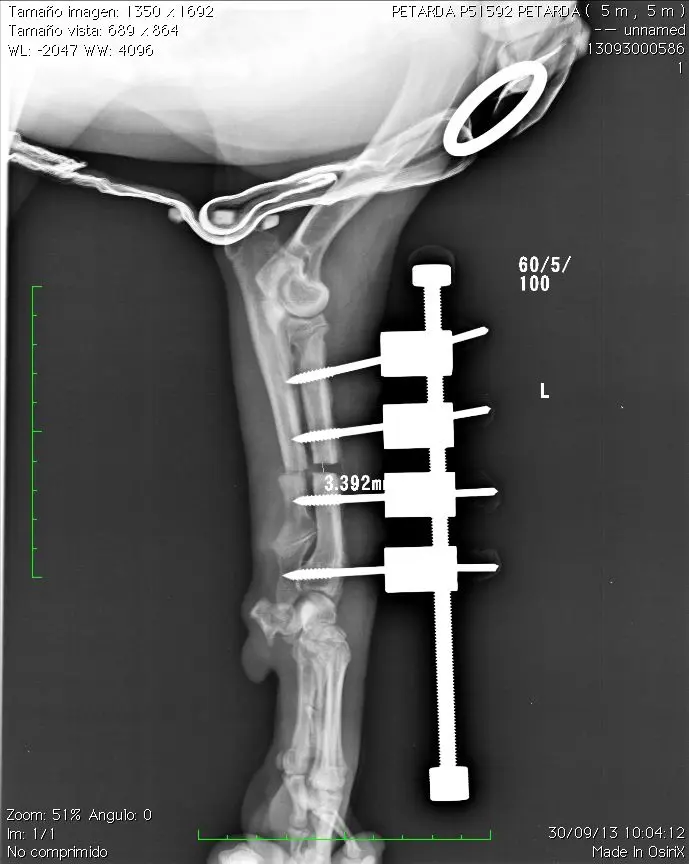

Deben realizarse radiografías semanalmente para comprobar que la distracción es efectiva

16-11-13 Cuando ambas extremidades tienen la misma longitud finalizamos la distracción aunque podemos continuar unos mm mas ya que la extremidad no afectada continuará su crecimiento. Muchos perros de unos 15 kg toleran discrepancia de 2 cm o más entre ambas extremidades sin sintomatología

Aspecto del hueso el 9-12-13. Observese la perfecta congruencia articular del codo. La articulación carporadial está anquilosada pero no presenta dolor